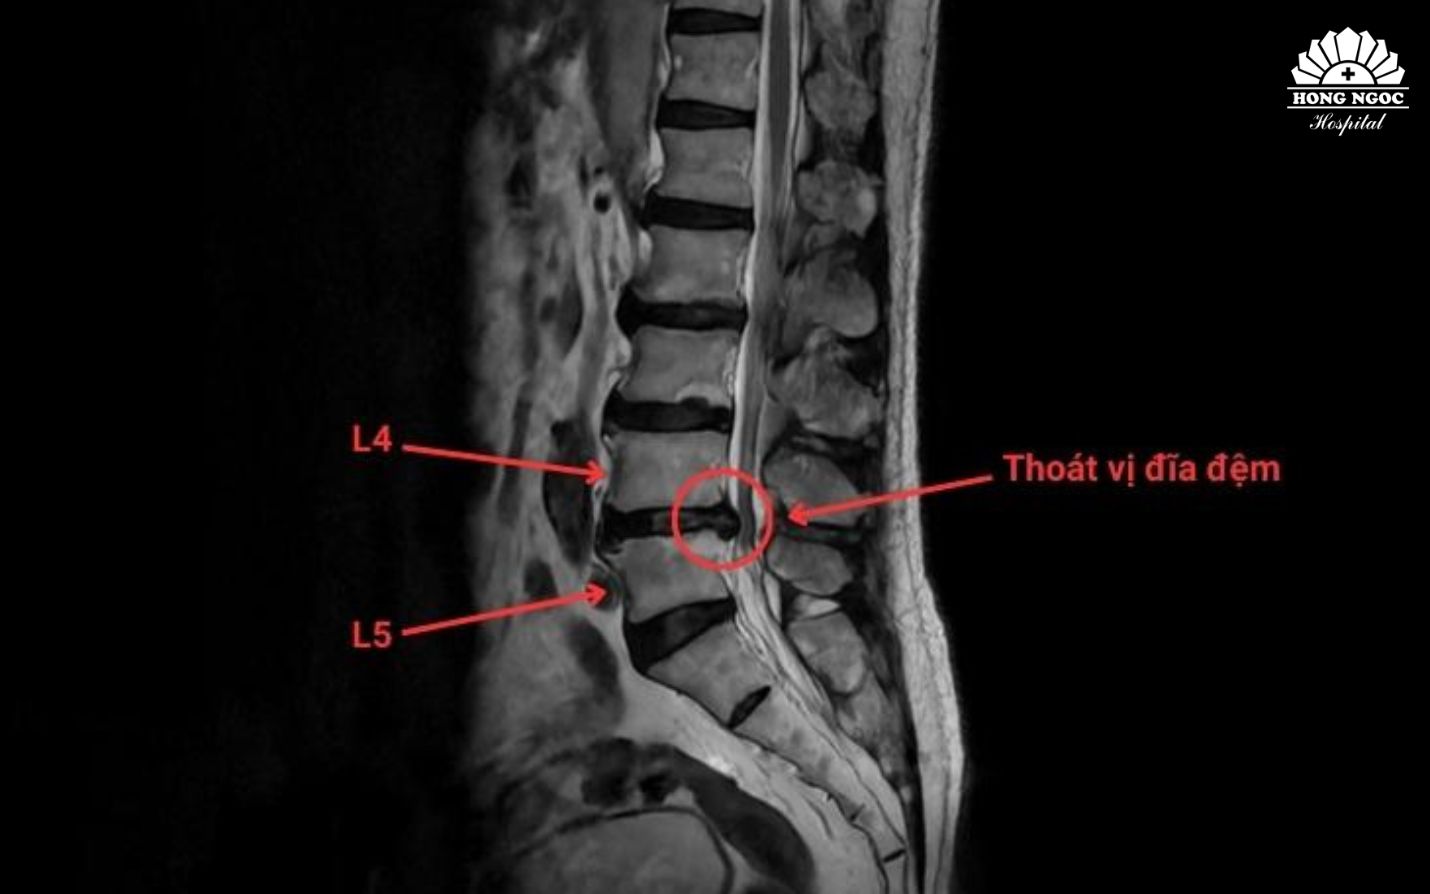

Phim chụp thoát vị đĩa đệm cột sống thắt lưng L4/L5

TS.BS Trịnh Tú Tâm (Trưởng khoa Chẩn đoán hình ảnh và Điện quang can thiệp, BVĐK Hồng Ngọc - Phúc Trường Minh) cho biết: Thoát vị đĩa đệm là tình trạng nhân nhầy thoát ra khỏi vị trí ban đầu qua vết rách bao xơ, chèn ép vào rễ thần kinh và gây nên những cơn đau cấp và mạn tính. Trong điều trị, các phương pháp can thiệp điện quang ít xâm lấn đang trở thành xu hướng hiện đại, được áp dụng rộng rãi tại nhiều quốc gia trên thế giới. Dưới hướng dẫn của hệ thống chẩn đoán hình ảnh, bác sĩ can thiệp tiếp cận chính xác vị trí tổn thương để xử lý nhân nhầy hoặc giảm chèn ép rễ thần kinh mà không cần phẫu thuật mở. Phương pháp này giúp điều trị tận căn nguyên, giúp giảm đau nhanh, phù hợp với người cao tuổi hoặc có nhiều bệnh lý nền.